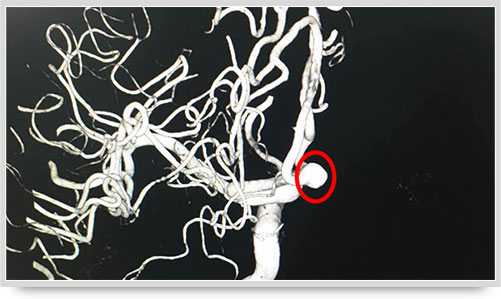

45岁的朱姓患者因“多发性腔性脑梗塞”头晕不明,接受了全脑血管造影术,术中显示他的颅内椎动脉血管痉挛(红圈内为病变部位)。据李主任介绍,以前像脑梗塞等脑血管疾病只能被定位到脑的功能区域,无法确定责任血管,而实施全脑血管造影术就能精准地找出病变血管,好比揪出了造成脑梗塞的“祸首”,大大提高了脑血管疾病的诊治水平。